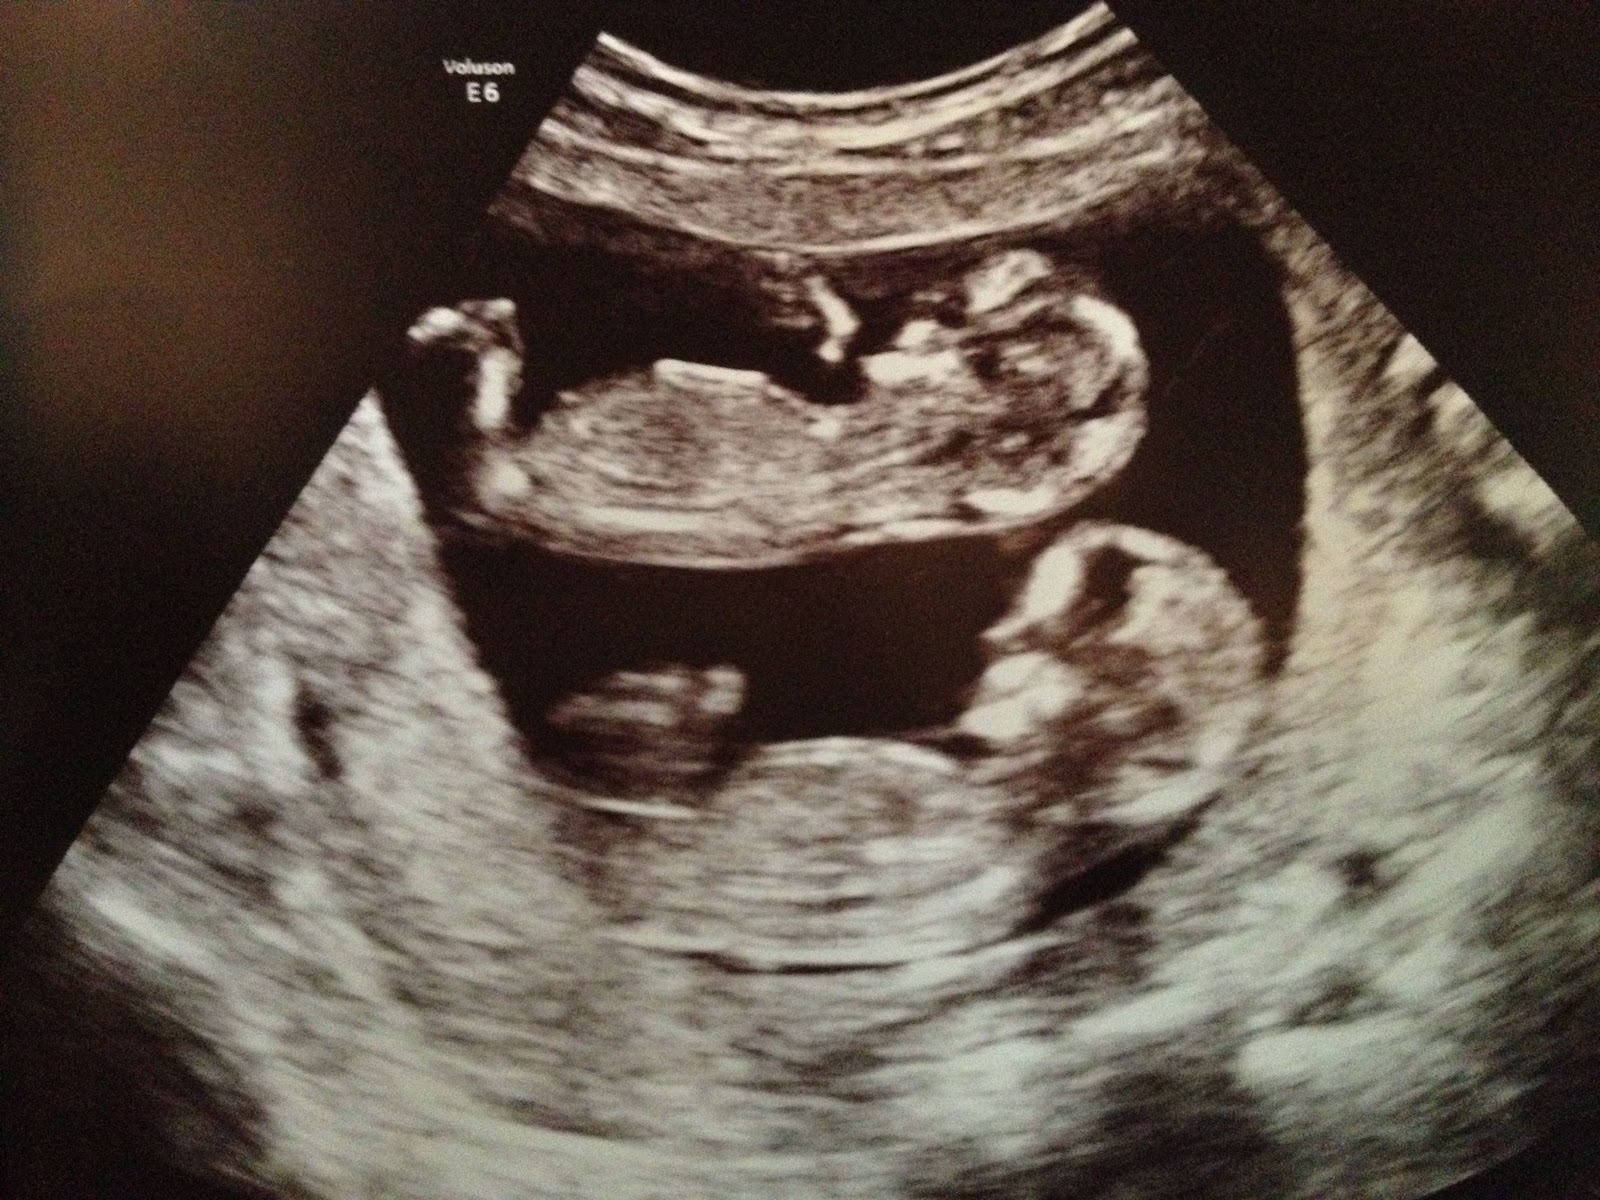

Sonogram Picture Of Identical Twins . Your ultrasound scan has shown that you are expecting twins that are monochorionic (shared placenta) or identical twins. Ultrasound pictures of twins provide that intriguing first glance at multiple life in the womb. A prenatal ultrasound is also called a sonogram and is a noninvasive diagnostic test. 10 week ultrasound of identical twins. You’ll be able to see for. All stages of twin pregnancy sonograms. There are a few variations of identical twins: Also called monoamniotic twins, these identical twins or triplets share. Check out hundreds of amazing twin ultrasound images! View the largest library of twins ultrasound images on the web. Sound waves are used to create a visual image of your babies, placenta, and uterus. A twin pregnancy can be broadly categorized into: Ultrasound assessment of fetal biometry, anatomy, doppler velocimetry and amniotic fluid volume is used to identify and monitor twin pregnancies at.

Sonogram Picture Of Identical Twins A prenatal ultrasound is also called a sonogram and is a noninvasive diagnostic test. 10 week ultrasound of identical twins. View the largest library of twins ultrasound images on the web. A twin pregnancy can be broadly categorized into: Ultrasound pictures of twins provide that intriguing first glance at multiple life in the womb. Your ultrasound scan has shown that you are expecting twins that are monochorionic (shared placenta) or identical twins. Check out hundreds of amazing twin ultrasound images! Ultrasound assessment of fetal biometry, anatomy, doppler velocimetry and amniotic fluid volume is used to identify and monitor twin pregnancies at. Sound waves are used to create a visual image of your babies, placenta, and uterus. A prenatal ultrasound is also called a sonogram and is a noninvasive diagnostic test. All stages of twin pregnancy sonograms. You’ll be able to see for. Also called monoamniotic twins, these identical twins or triplets share. There are a few variations of identical twins: